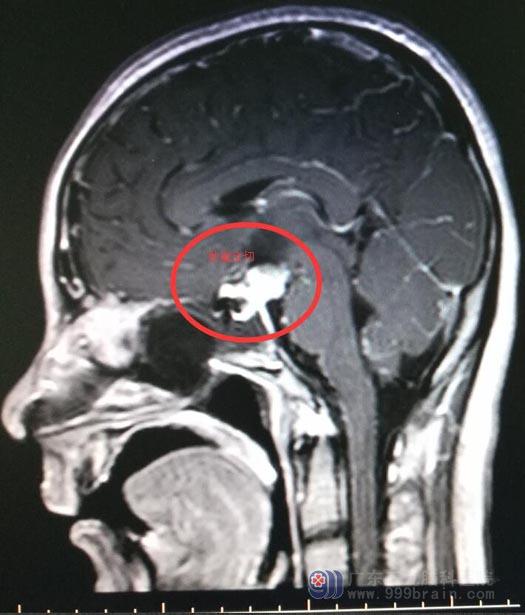

术后MR 白色部分为填塞的脂肪